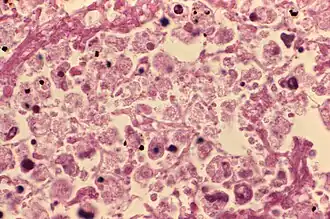

![]() Microfotografía electrónica de barrido (SEM), con magnificación de 8000X, con grupo de bacteria Gram-negativa Legionella pneumophila | ||